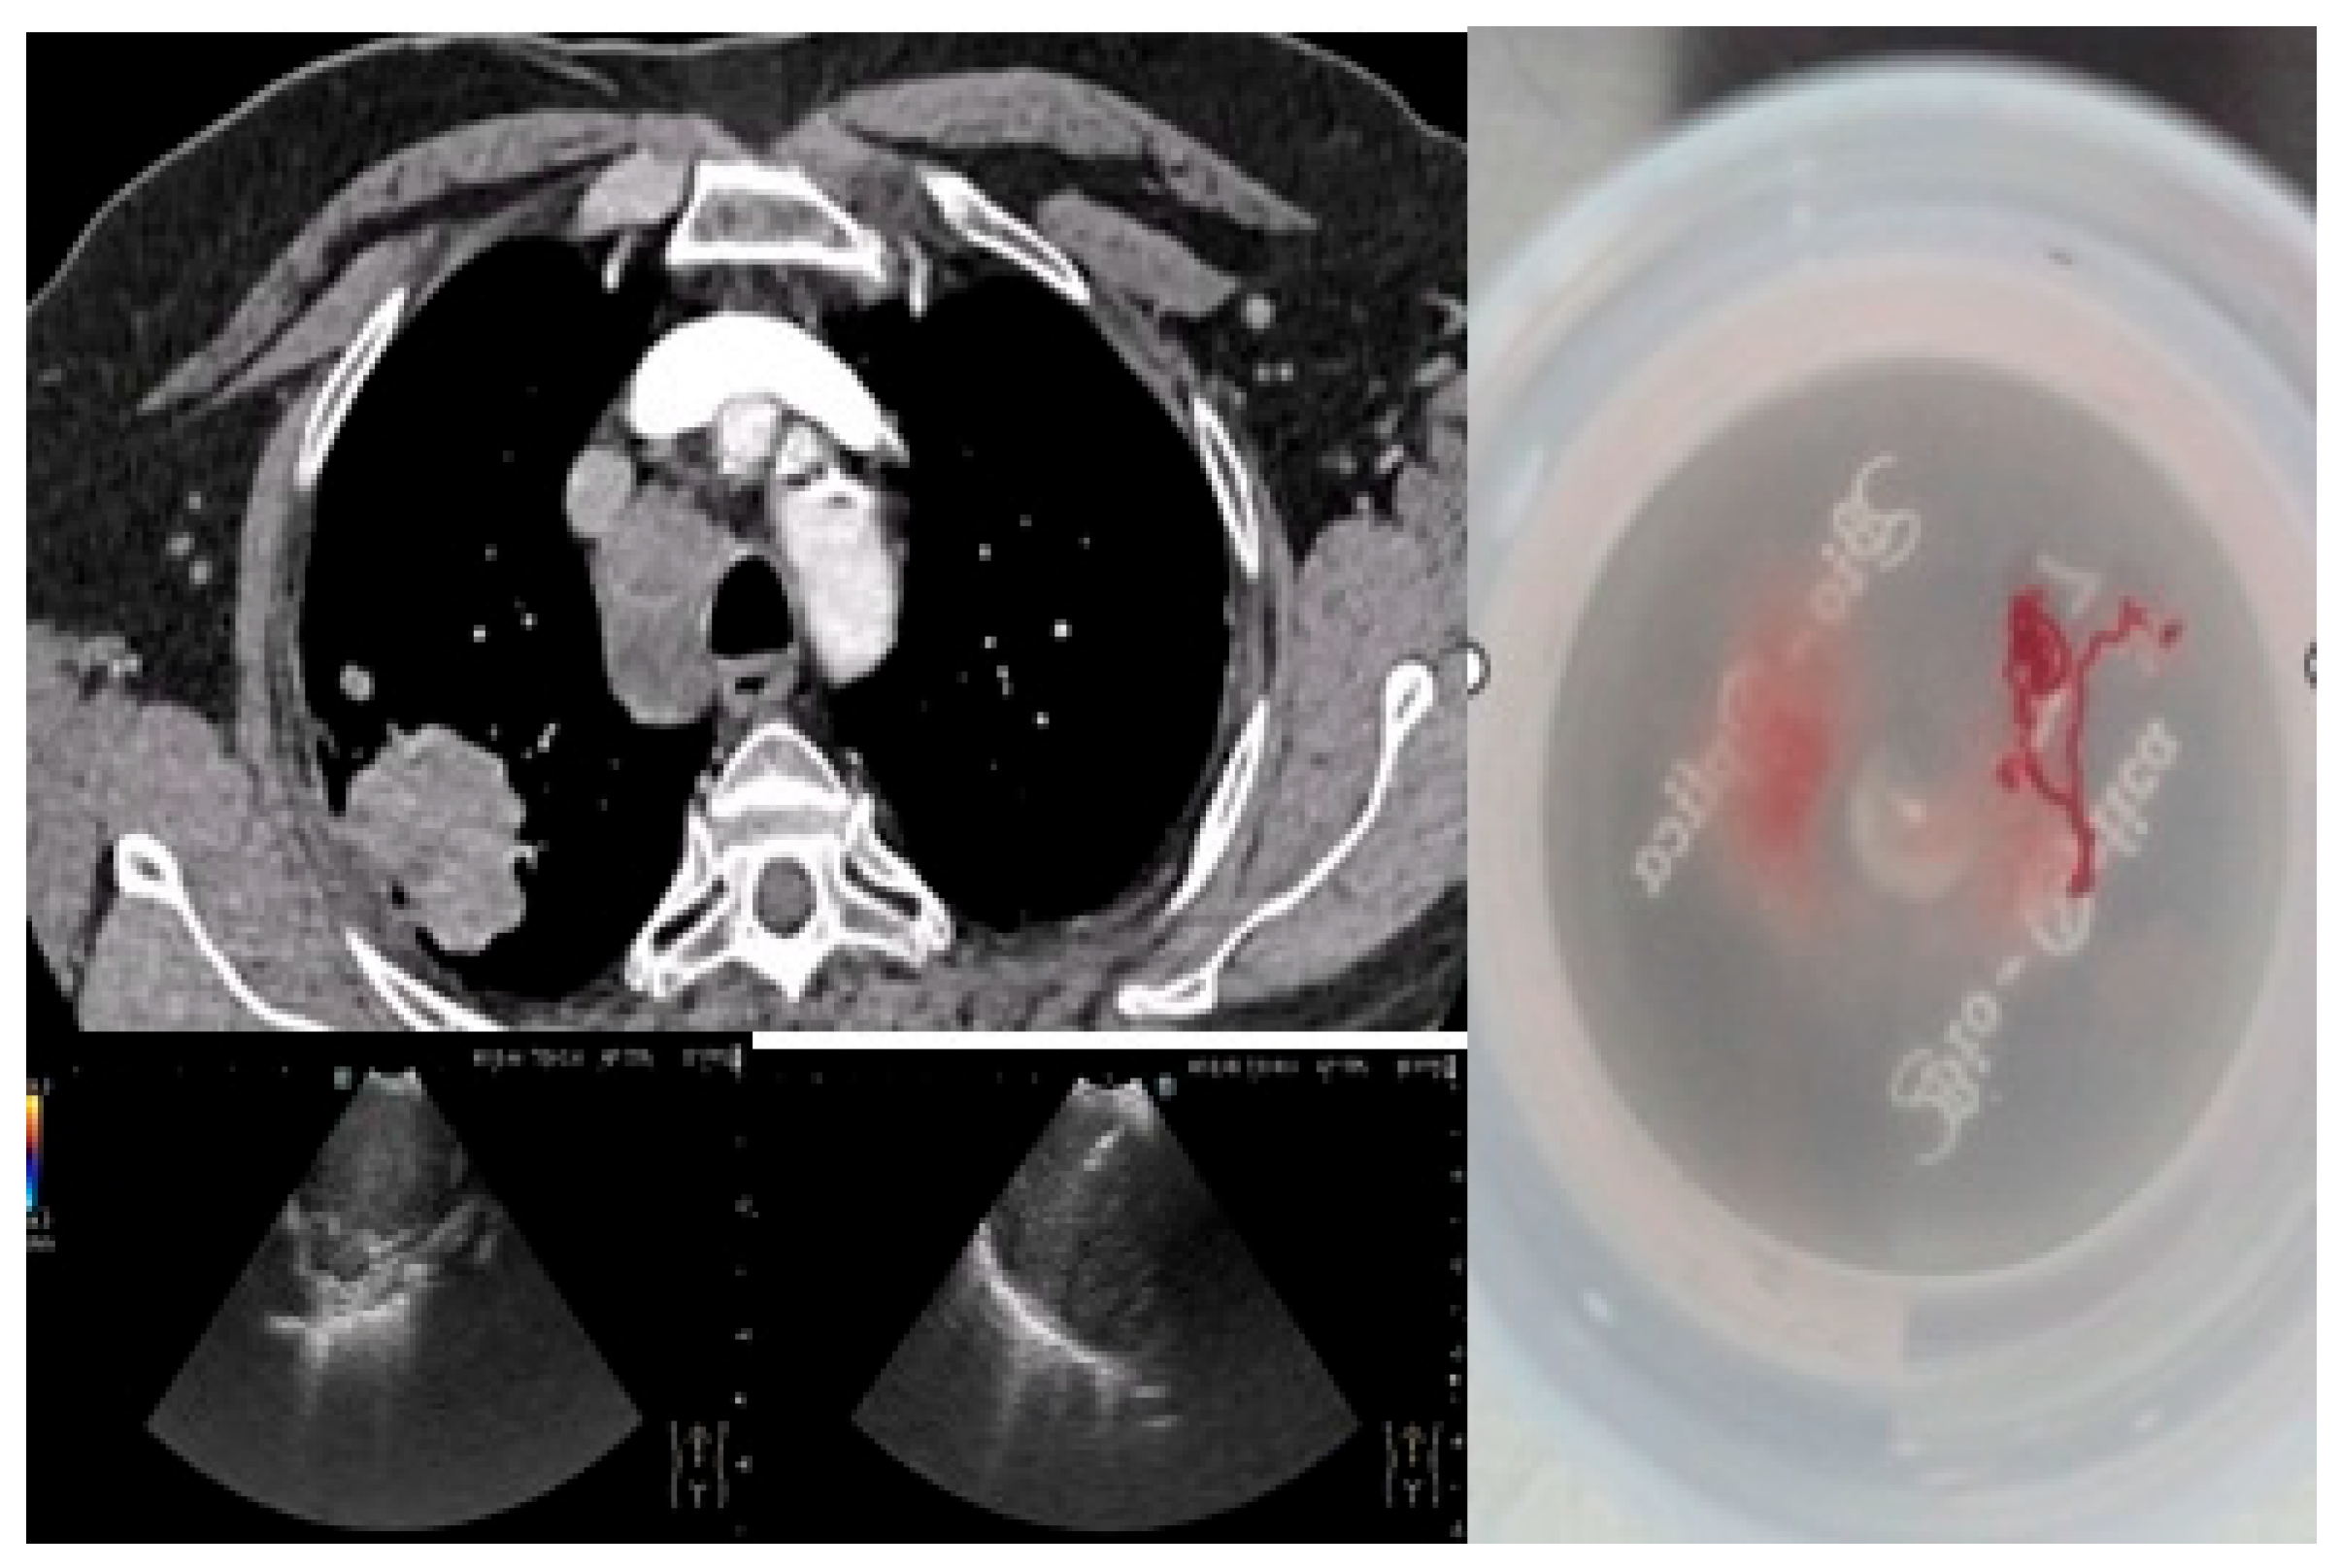

All patients (100%) underwent bronchoscopy, while EBUS-TBNA was performed in 42 patients (62.7%) with mediastinal lymphadenopathy detected on imaging. No significant complications related to either procedure were reported, confirming the safety of the proposed algorithm. Figure 1 illustrates a representative bronchoscopic finding in a 72-year-old ex-smoker male with an adenocarcinoma of the dorsal segment of the right upper lobe, showing well-vascularized tissue with distal bronchial invasion and significant stenosis due to extrinsic compression and mucosal infiltration. Figure 2 depicts an EBUS-TBNA procedure in a 69-year-old ex-smoker male without endobronchial tumor expression, performed under local anesthesia and mild sedation at station 4R, with a final diagnosis of small cell carcinoma confirmed by immunohistochemistry (thyroid transcription factor-1 (TTF1) positive, synaptophysin (SYN) positive, Ki67 proliferation index 98%).

Figure 1. Bronchoscopic image (institutional archive): (a) 12 December 2023; (b) 16 January 2024.